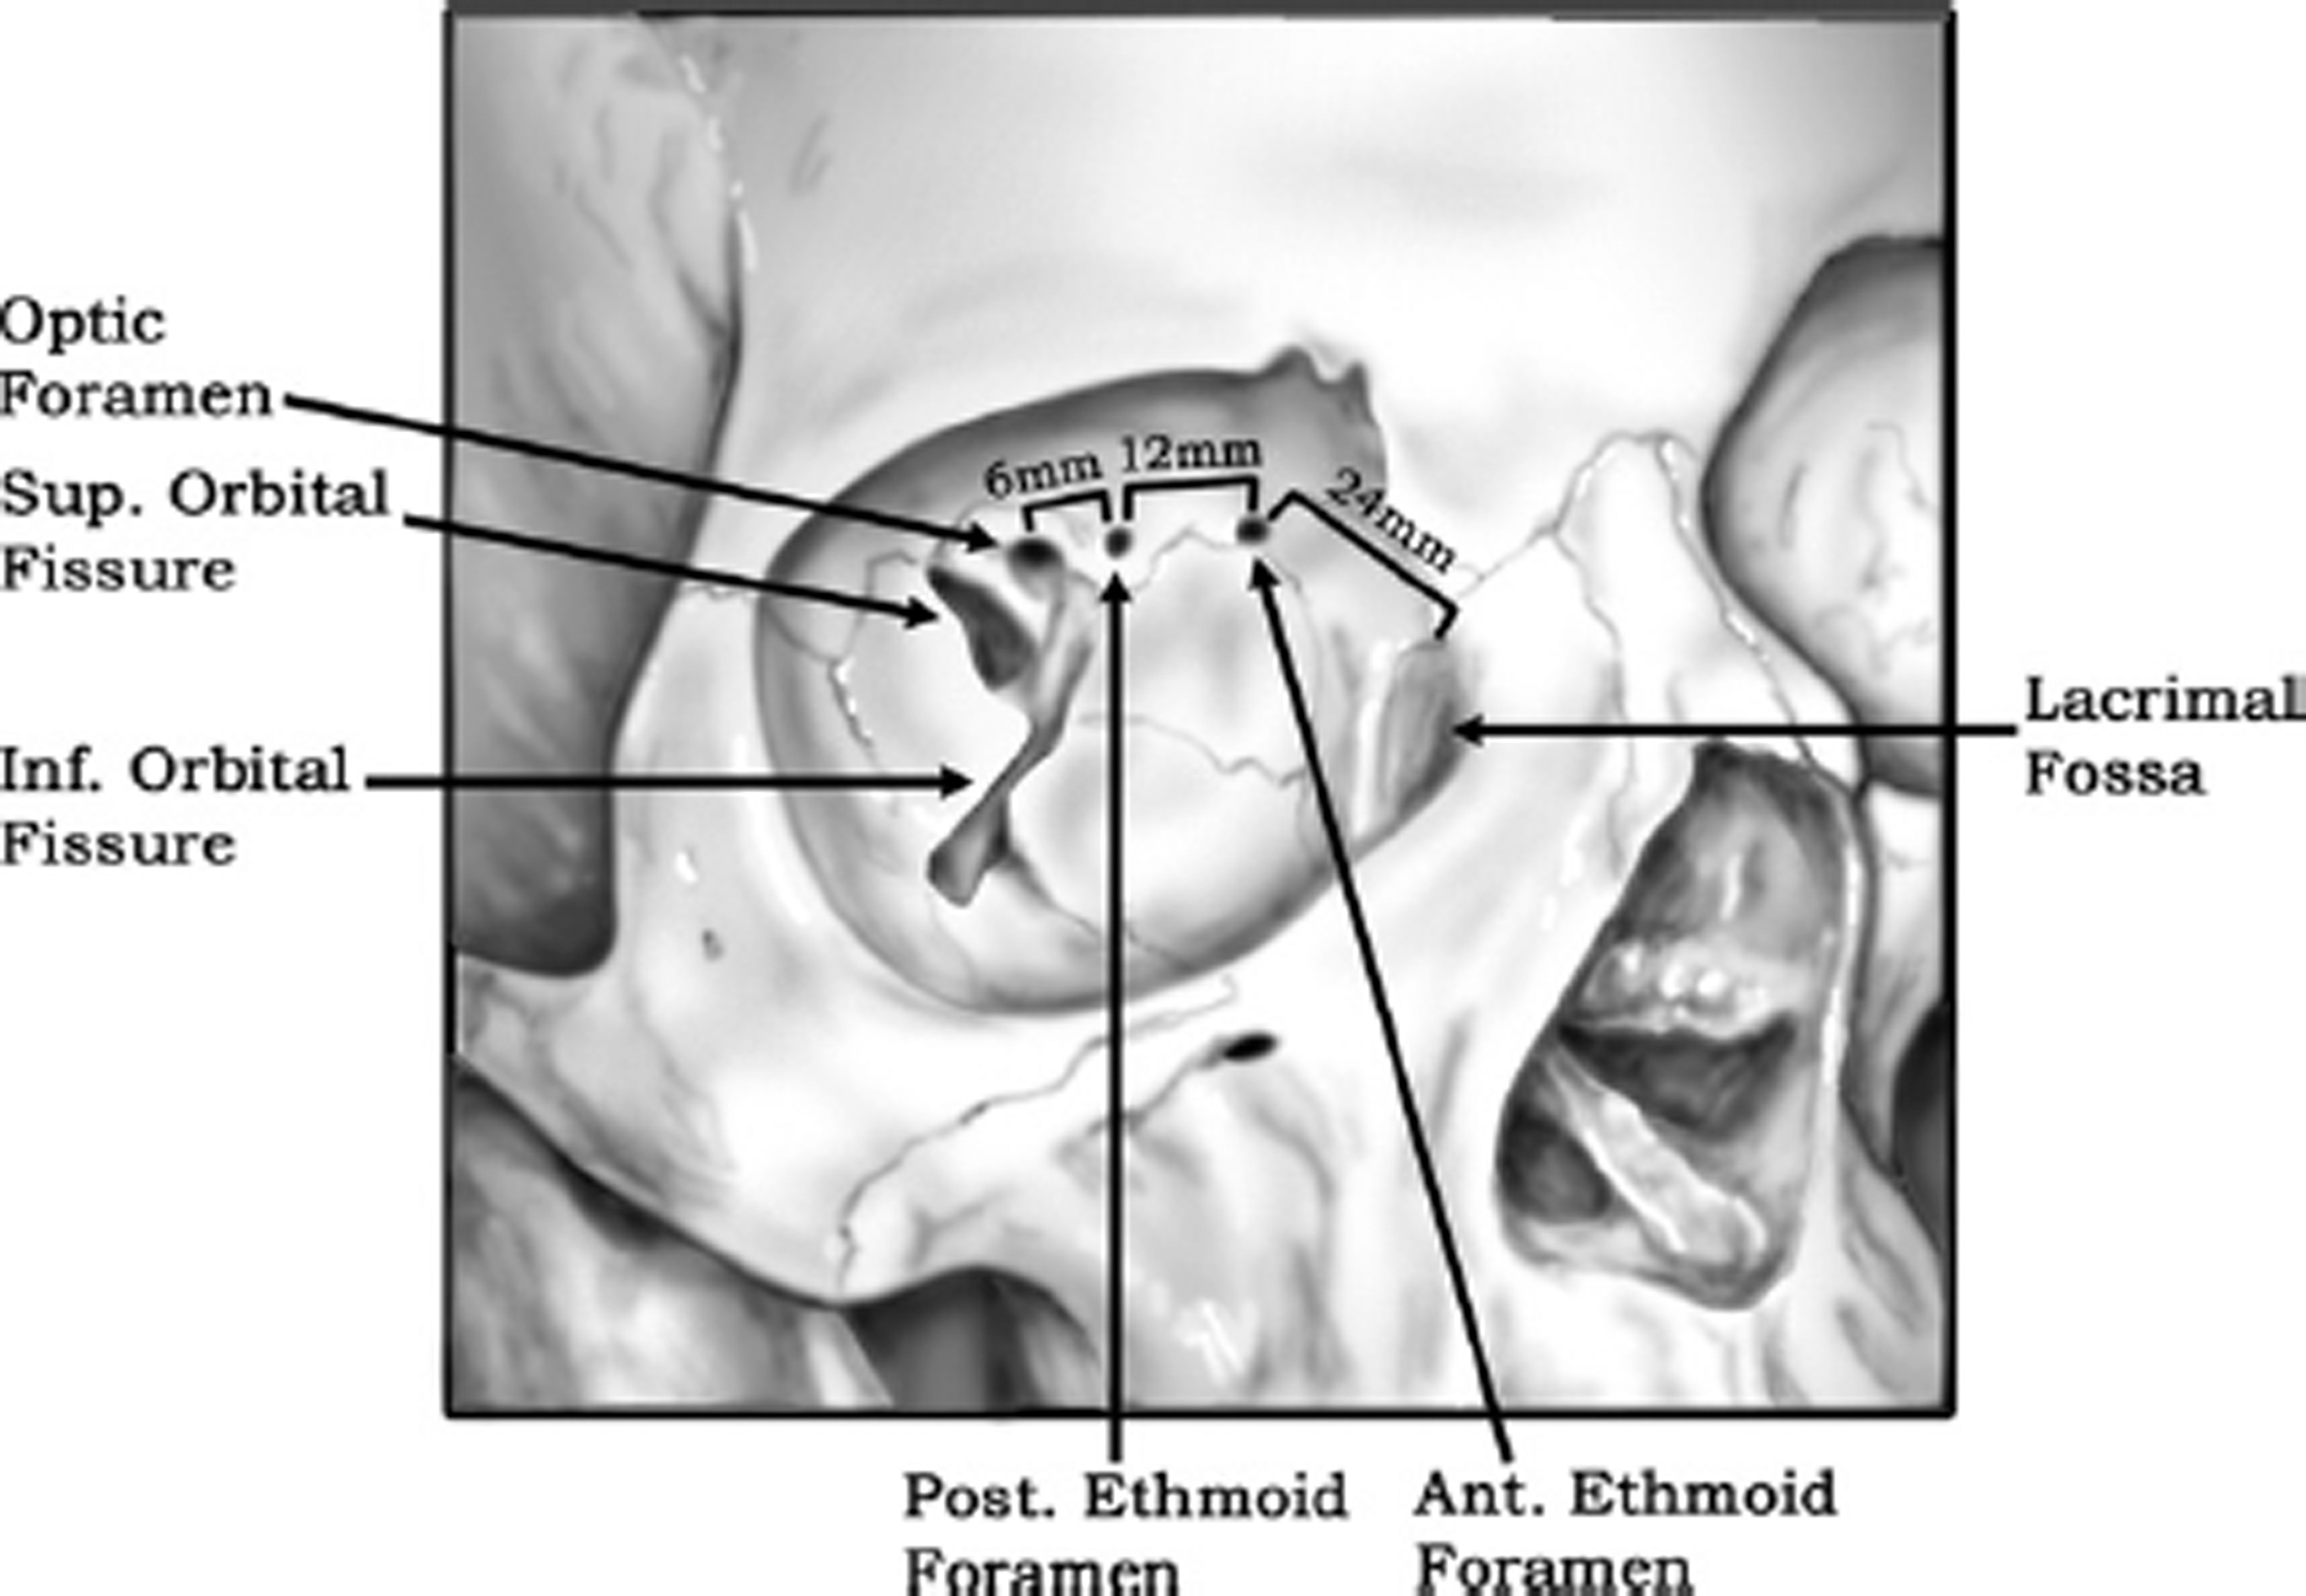

The medial orbital wall is the thinnest of all orbital walls. It is formed by the maxillary, ethmoid, lacrimal, and sphenoid bones. It is thinnest along the lamina papyracea of the ethmoid bone. The ethmoid bone joins with the orbital roof at the frontoethmoidal suture line. It is at this point where anterior and posterior ethmoid foramina are located. Their respective ethmoidal arteries course through these foramina after branching from the ophthalmic artery. The anterior ethmoid neurovascular bundle is typically 20 to 25 mm posterior to the lacrimal crest, whereas the posterior ethmoid neurovascular bundle is another 12 mm posterior to the anterior foramina. The optic canal typically lies 4 to 8 mm posterior to the posterior foramina ( Fig. 3 ). Medial wall fractures can occur in isolation or in combination with orbital floor fractures. Inferiorly, the medial orbital wall transitions to the thick orbital strut bone which is often resistant to fracture.